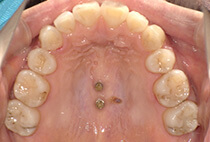

しっかり前歯を下げるために、インプラントアンカーを使用してコントロールしました。

治療後